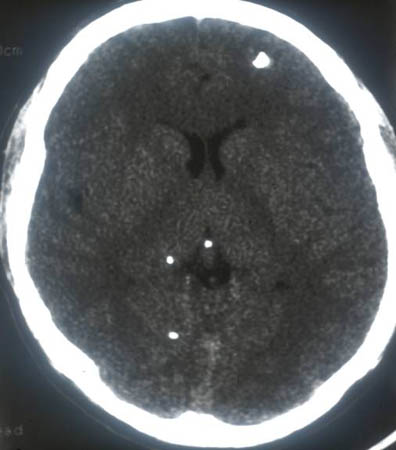

RNM cranioencefálica/da coluna

Exame

A neuroimagem é a base do diagnóstico para a neurocisticercose. A RNM é superior à TC na identificação de cistos extraparenquimatosos e lesões da fossa posterior, mas a TC é melhor na visualização de cistos calcificados.[39] A RNM também pode revelar o escólex que, geralmente, não é visível em TCs. Idealmente, ambos os testes devem ser considerados.

Achados específicos dependem da localização dos cistos (consulte tomografia computadorizada do cérebro, acima).[33][40]

Todos os pacientes com doença subaracnoide devem fazer uma RNM da coluna.[33][Figure caption and citation for the preceding image starts]: Estádio cístico - neurocisticercose: ressonância nuclear magnética (RNM) mostrando lesão cística no lobo frontal; é possível observar um escólex no interior do cistoDo acervo da Dra. Christina Coyle e do Dr. Maheen Saeed; usado com permissão [Citation ends].

[Figure caption and citation for the preceding image starts]: Estádio calcificado - neurocisticercose: RNM de várias lesões calcificadas em um paciente com neurocisticercoseDo acervo da Dra. Christina Coyle e do Dr. Maheen Saeed; usado com permissão [Citation ends].